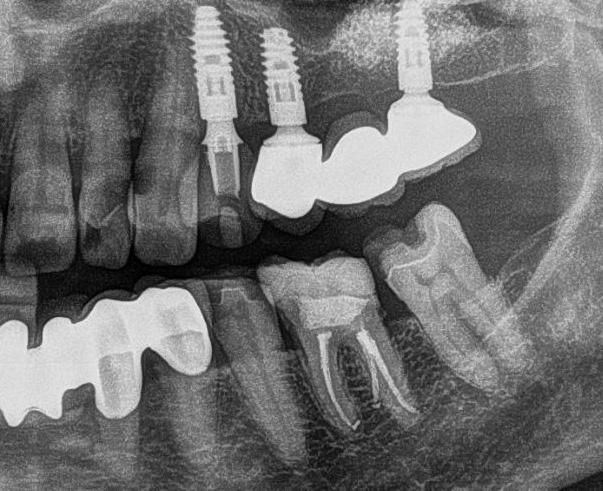

Kiindulási szituáció Egy 49 éves, nem dohányzó, egészséges férfi páciens jelentkezett a rendelőnkben hiányzó 2.6-os és 2.7-es foggal, valamint azzal a panasszal, hogy már lassan egy hete, lüktető fájdalmat érez a 2.5-ös fogánál. Megoldást keresett a hiányzó fogak pótlására is. Klinikai intraorális vizsgálat alapján a 2.5-ös fogon egy sérült fémkerámia korona volt,

1. ábra: Megfelelő szájhigiénia – panorámaröntgen. 2. ábra: A 2.5, 2.6 és 2.7-nek megfelelő terület a röntgenfelvételen.

és jelentős mobilitással rendelkezett. A radiológiai vizsgálat után egyértelműen látszódott, hogy a fogon még nem végeztek gyökérkezelést. A 2.6-os és 2.7-es fogaknak megfelelő területen az arcüreg kiterjedése jelentős volt, vertikális csontmennyiség szignifikánsan csökkent (1. és 2. ábra).

A végső röntgenfelvételen láthatjuk az osszeointegrálódott implantátumokat, valamint a stabil kresztális gerincet az azonnal behelyezett, a rövid és a ferde, a tuberben elhorgonyzott implantátum körül (12. ábra).